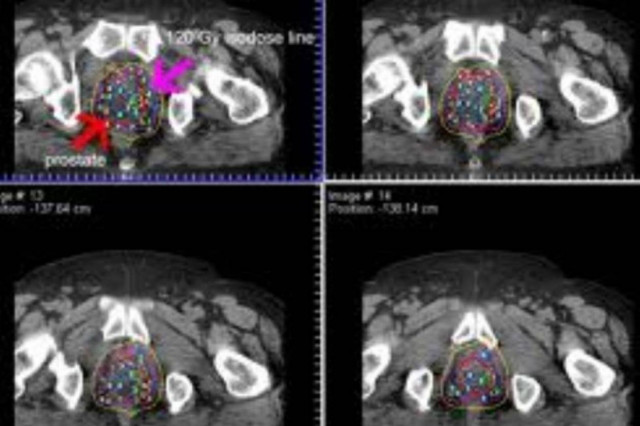

ΚΑΡΚΙΝΟΣ ΤΟΥ ΠΡΟΣΤΑΤΗ

Καρκίνος του προστάτη: Μπαίνει σε τροχιά ίασης η νόσος